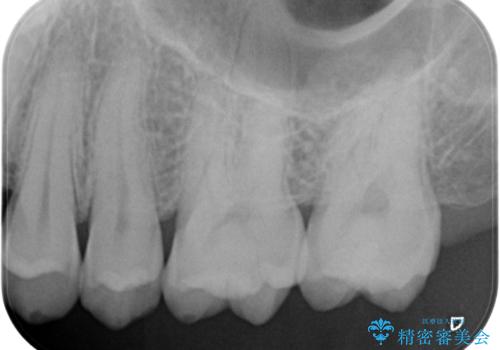

- 検査の結果、奥歯の咬む面に小さな虫歯が確認された患者様です。

虫歯を除去し、セラミックインレーでの修復処置を行います。

表面からは小さな虫歯かのように見えましたが、実際虫歯を取っていくとある程度の大きさがありました。

咬む面の溝は虫歯の好発部位となっています。気を付けて歯磨きができると良いです。